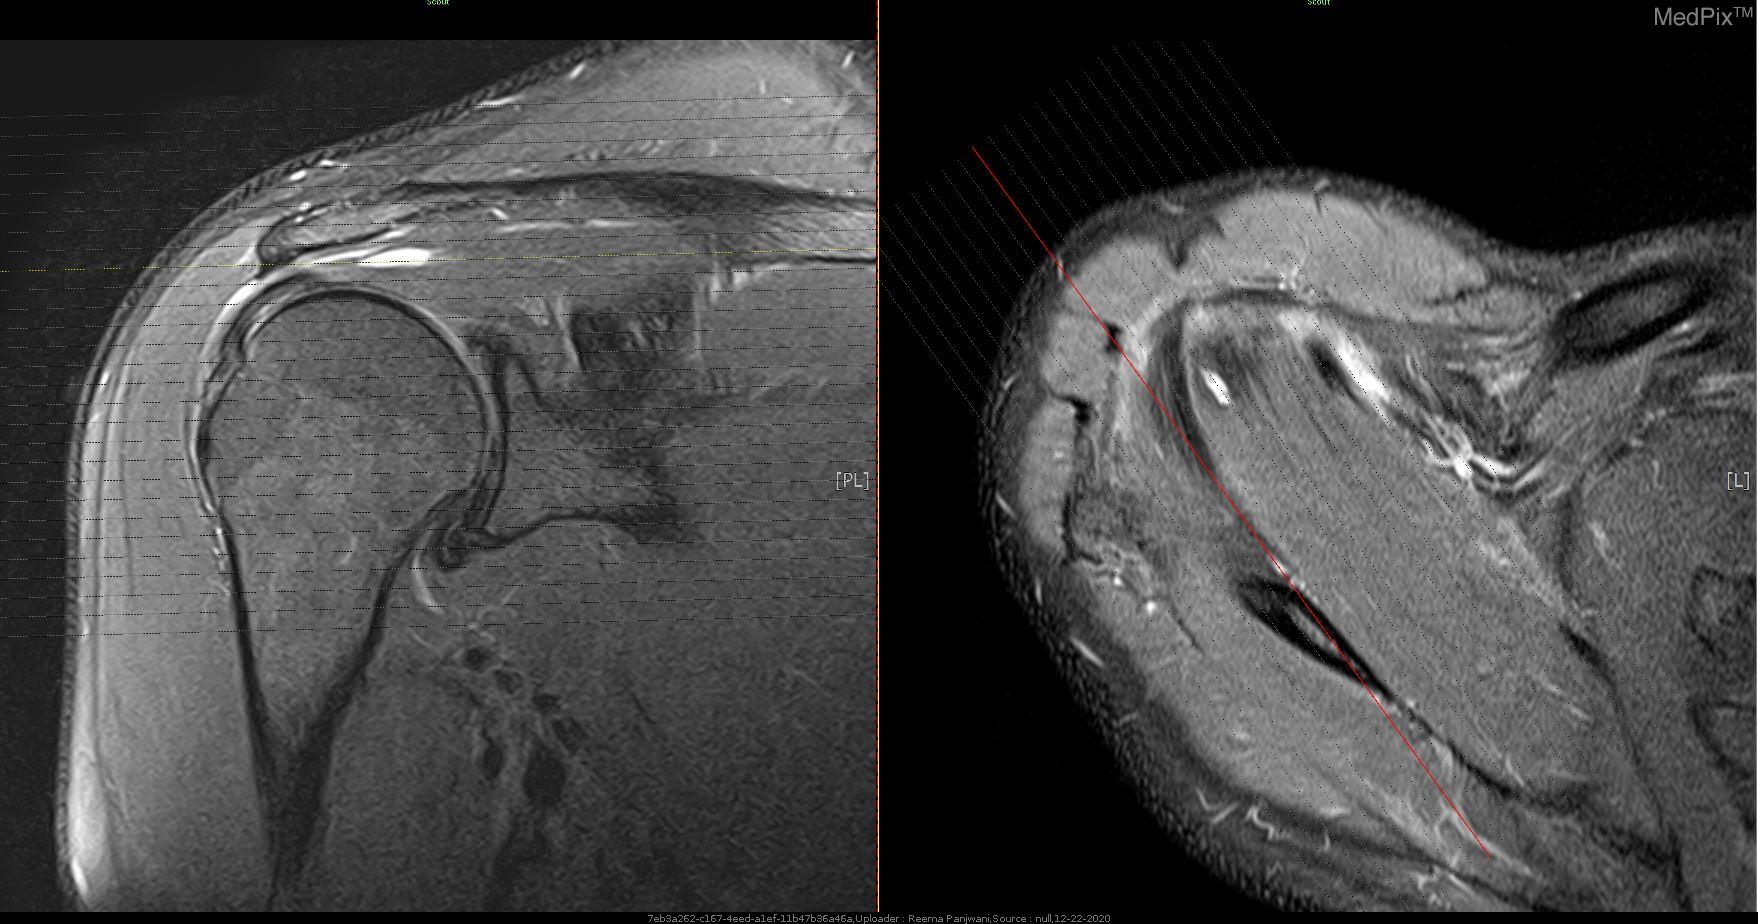

The rotator cuff is a group of four shoulder muscles that help to promote proper shoulder mechanics and center the head of the humerus bone in the shoulder blade socket, enabling optimal shoulder movement without pain. Any of the four rotator cuff muscles can develop a tear or strain, and this can be a sharp, traumatic episode or a slowly-developing occurrence over time. At Goodell PT, we can help diagnose a rotator cuff strain or tear, and develop a comprehensive exercise program to help strengthen and rehabilitate the involved muscle(s). There may also be contributing factors from the cervical and thoracic spine regions that we can identify and address in order to decrease strain forces on cuff itself.